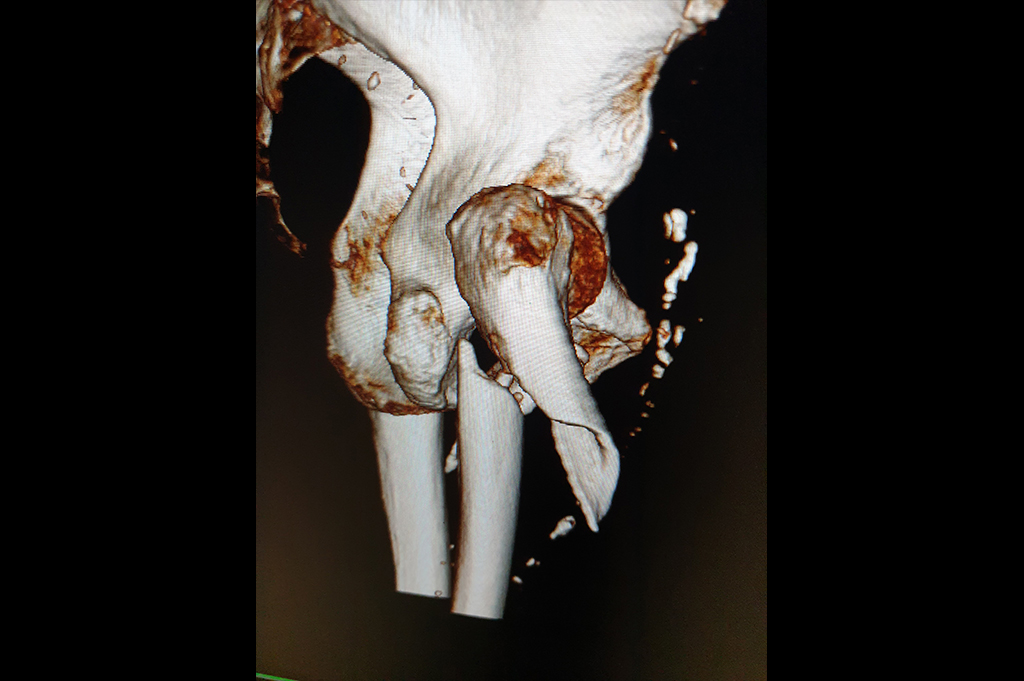

Proximal Humerus